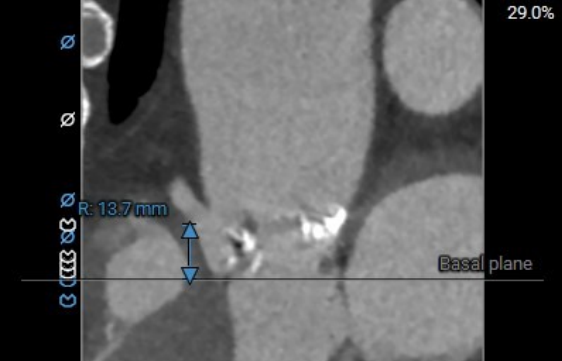

右冠高度:13.7mm

左冠高度:9.6mm

术前主动脉CTA评估:主动脉瓣三叶式,瓣叶基本等大,瓣叶增厚、黏连,瓣叶游离缘中-重度钙化,左-无、右-无交界钙化融合。主动脉瓣环周长折算直径约28.6mm;左侧冠脉开口高度稍低LCA:9.6mm,RCA:13.7mm;右冠及左冠分支轻度钙化;左室流出道轻度钙化。升主动脉增宽;双侧髂外动脉迂曲,余未见明显迂曲。

术前主动脉CTA评估:主动脉瓣二叶式type1型,L-R融合,瓣叶增厚、黏连,瓣叶游离缘、根部及融合脊中-重度钙化;主动脉瓣环周长折算直径约25.2mm;双侧冠脉开口高度可;双冠分支轻度钙化;术中建议造影角度LAO:9°,CRA:11°;左室流出道稍凸出;主动脉弓及降主动脉多发钙化,腹主动脉重度钙化。